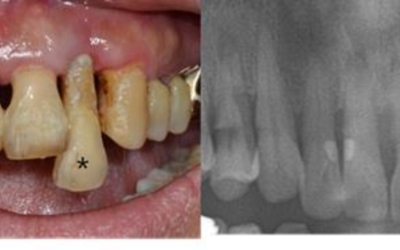

치주질환의 가장 저명한 원인은 치태와 치석입니다. 구강 내 음식물과 세균으로 인해서 치태가 형성되고, 제때 제거되지 못한 치태는 치석을 형성하고 결국 치주질환을 유발해요. 세균들이 잇몸에 염증반응을 유발하는 물질을 분비하고 이로 인해 잇몸이 붓고 잇몸에서 피가나는 증상이 생기는 것으로 보입니다.

잇몸에 발생되는 염증을 ‘치은염’이라고 부르고, 이 경우에 잇몸의 염증치료가 제때 되지 않아 염증이 악화되면 치주염으로 변하게 돼요. 증상이 악화되면 ‘치아상실’까지 초래할 수 있기 때문에 평소 잇몸관리는 필수입니다.